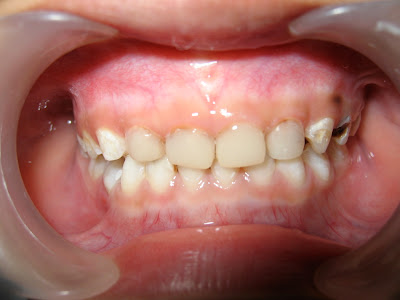

sim salabim… gigi si kecil dalam sekejap jadi putih…!!!

sekarang si kecil dapat tersenyum lebar tanpa malu2 karena giginya hitam… =D